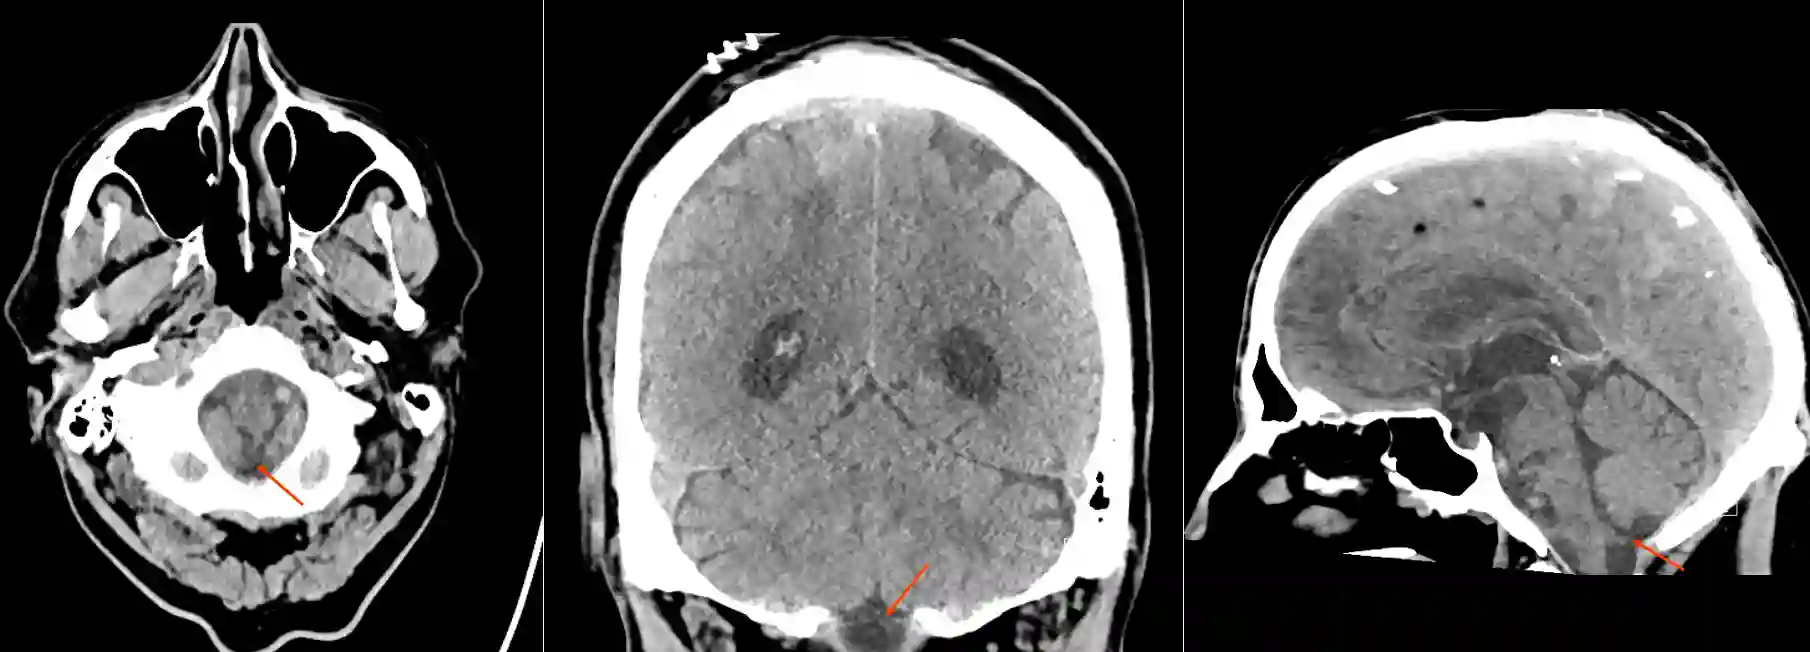

Cisterna cerebellomedullaris

Darstellung der Cisterna cerebellomedullaris (Cisterna magna) in der verschiedenen Ebenen in einer CT-Bildgebung des Schädels.